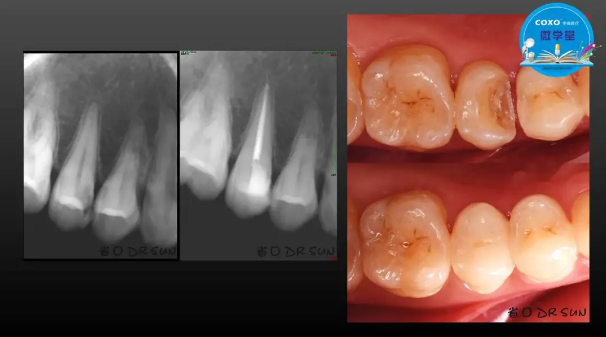

主任醫(yī)師,牙體牙髓副主任, 廣東省口腔醫(yī)院牙體牙髓科 主任醫(yī)師。2003年碩士研究生畢業(yè),研究方向?yàn)檠荔w牙髓病學(xué),擅長(zhǎng)于牙體牙髓病的診斷、齲齒、牙髓炎、根尖周病的治療以及前牙美容修復(fù)。